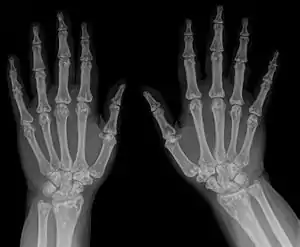

| Diagnostic method | X-ray, ultrasound[3] |

- Osteopoikilosis

- Metaphysis abnormality

Diagnosis

- X-ray